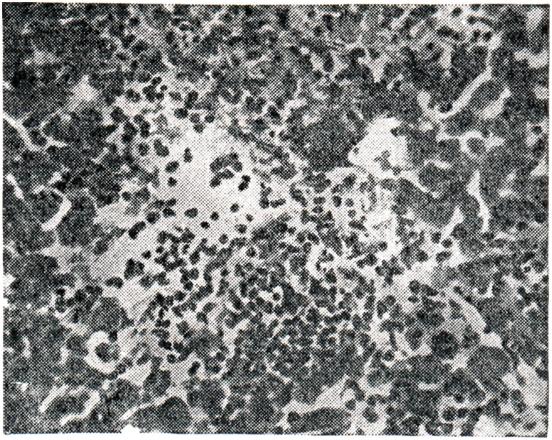

В ранней, миграционной фазе аскаридоза происходит сенсибилизация организма больного продуктами обмена паразита, а иногда и распада личинок аскарид, что приводит к возникновению эозинофильных и лимфо-гистиоцитарных инфильтратов, эндартериитов и микронекрозов в стенке кишечника, печени (рис. 5) и легких. Сенсибилизация больного продолжается, но в меньшей степени, и во время кишечной фазы аскаридоза. Личинки наносят повреждения тканям во время миграции, например разрывают измененные в результате аллергии капилляры в легких, обусловливая кровоизлияния. Взрослые аскариды травмируют и иногда перфорируют стенку кишечника концами своего тела. Клубки аскарид могут вызвать механический илеус, а раздражение нервных окончаний кишечника иногда приводит к спастической непроходимости его. К весьма тяжелым последствиям приводит проникновение аскарид в печень, поджелудочную железу, органы дыхания. Экспериментальной моделью ранней миграционной фазы аскарид является морская свинка, которой скармливают инвазионные яйца аскарид. Личинки мигрируют в теле морской свинки, но никогда не достигают здесь половой зрелости. Эти эксперименты показали, что при повторных заражениях число мигрирующих личинок по сравнению с первичным заражением значительно сокращается, уменьшается их размер и срок пребывания в организме хозяина; патологоанатомические изменения в органах при повторном заражении выражены слабее, чем при первичном. При многократном заражении личинки погибают на самом раннем этапе развития, не достигая легких. Все это говорит о развитии у животных иммунитета, который имеет клеточную и гуморальную природу. Через 5—10 дней после заражения аскаридозом в крови хозяина появляются антитела, обнаруживаемые в течение 80—90 дней реакцией преципитации. Последняя бывает положительной и с сывороткой крови людей, перенесших миграционную фазу аскаридоза; она становится у них отрицательной через 3 месяца после заражения. В крупных очагах аскаридоза у людей создается иммунитет к суперинвазии — около 25% заражений заканчивается на ранней стадии развития гельминтов. Интенсивность инвазии у приезжих из районов, где аскаридоз не имеет широкого распространения, через некоторое время становится выше, чем у аборигенов.

Рис. 5. | ||